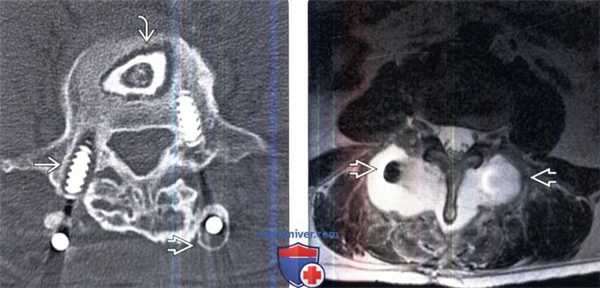

(Слева) Аксиальный срез, КТ-срез: признаки дестабилизации обоих педикулярных винтов, наиболее выраженные в средней и дистальной их части. Прозрачная зона и признаки ремоделирования кости также видны в области продольного стержня. Прозрачная зона вокруг костного трансплантата на уровне L3-L5 свидетельствует об отсутствии его интеграции.

(Справа) Аксиальный срез, Т2-ВИ: пациент, которому ранее были выполнены ляминэктомия и PLIF вокруг задней металлоконструкции видна патологическая жидкостная зона, распространяющаяся в паравертебральные ткани и представляющая собой послеоперационное псевдоменингоцеле.